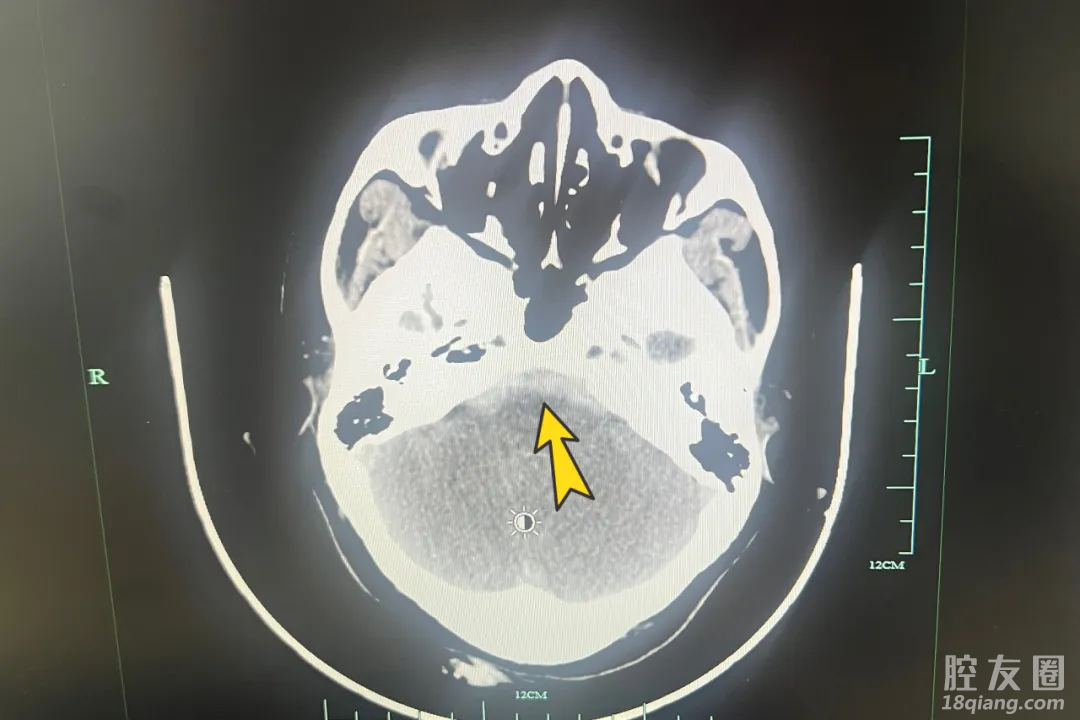

到达医院时,汪女士已经昏迷无意识,医护人员第一时间给予补液、控制血压、呼吸机辅助呼吸等措施。急诊影像检查提示“脑动脉夹层伴蛛网膜下腔出血”,神经外科主任朱志刚迅速作出判断,考虑脑动脉瘤破裂。

经过紧急行脑血管造影,明确右侧椎动脉夹层动脉瘤破裂伴蛛网膜腔下出血。少一份等待,多一分救治,在和家属充分沟通后,朱志刚决定立即为汪大姐实施右侧椎动脉瘤栓塞术。